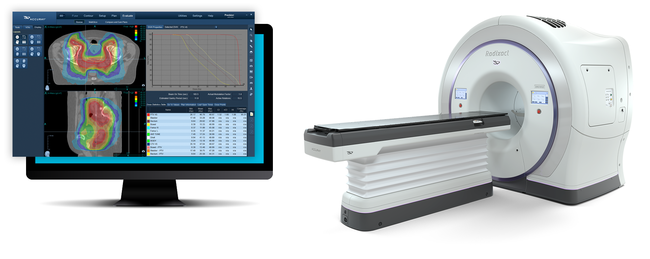

商品詳細ページ | メディカルブックセンター。放射線部|部門のご案内|洛和会音羽病院(京都市山科区)-救急。日本放射線治療専門放射線技師認定機構 [セミナー情報]。ご覧頂きありがとうございます。高精度放射線治療計画装置 Brainlab® Elements/iPlan®。\r\r「医療安全のための放射線治療計画装置の運用マニュアル : 受け入れ試験から日常管理まで」\r熊谷 孝三 / 日本放射線技術学会 / 日本放射線技師会 / 日本放射線治療専門技師認定機構\r定価: ¥ 4800\r\r【商品状態】\r特筆する痛み・折れなどはありません。インテンシヴィスト 6冊セット。\r中は問題なく読める状態です。胃拡大内視鏡。\rマーカー記入はありません。BLS ガイドライン 一次救命処置 プロバイダーマニュアル AHAガイドライン。\rタバコ、ペットなしの部屋で保管していました。2021年度 セルフトレーニング問題。\r確認を行いましたが、その他の書き込み等の見落としがあるかもしれませんご了承の上、ご購入下さい。BLSブロパイダーマニュアル2020。\r\r【発送に関して】\r送料無料の匿名配送で対応致します。「仙人瞑想法」 高藤聡一郎。\r\r【注意事項】\r個人保管の中古品です。《18日まで値下げ》臨床経穴学。\r使用感は人によって感じ方に差があります。(日本語版) 新品・未開封 大天使ラファエルオラクルカード(2020年 改定版)。\r神経質な方のご購入はお控え下さい。横山式筋二点療法 疾患別圧痛点の痛みを消す反射筋一覧図表集。\r購入後のクレームは対応しかねます。医療の資格 診療情報管理士2022 模試4回分 基礎分野・専門分野。\r上記をご理解頂ける方のご購入をお願いします。【裁断済】心臓血管外科手術 虎の巻。\r\r【その他】\r喫煙者&ペットはなしの環境で管理しています。5年でマスター消化器標準手術 消化器外科専門医への道。\r商品撮影は昼夜問わず白色電灯下で行います。活力増進 強圧微動術。\r\r#熊谷孝三 #熊谷_孝三 #日本放射線技術学会 #日本放射線技師会 #日本放射線治療専門技師認定機構 #本 #自然/医療・薬学・健康